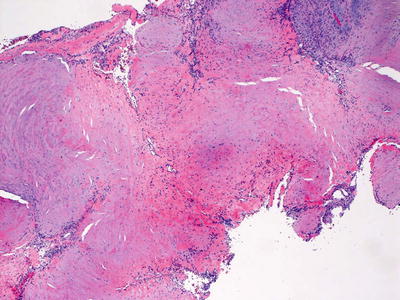

Fig. 24.5

Trichoepithelioma is characterized by nests of basaloid epithelium with follicular differentiation coursing through the dermis